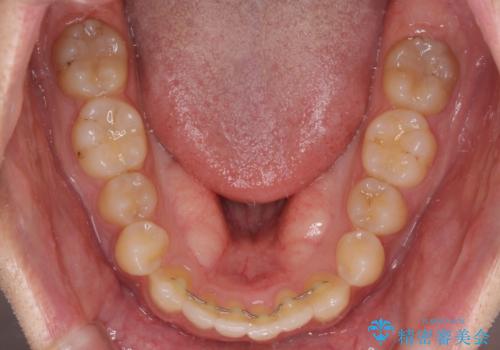

- 上下前歯のデコボコと深い咬み合わせを気にして来院された患者様です。

インビザラインによる上下歯列の拡大と、IPR(歯と歯の間を削る)にるスペースの獲得により、前歯のデコボコとディープバイトを改善することとしました。

もう少し下の前歯を整えたかったのですが、患者様の治療を早く終了させたいという希望により、細かい叢生を残しての終了となりました。